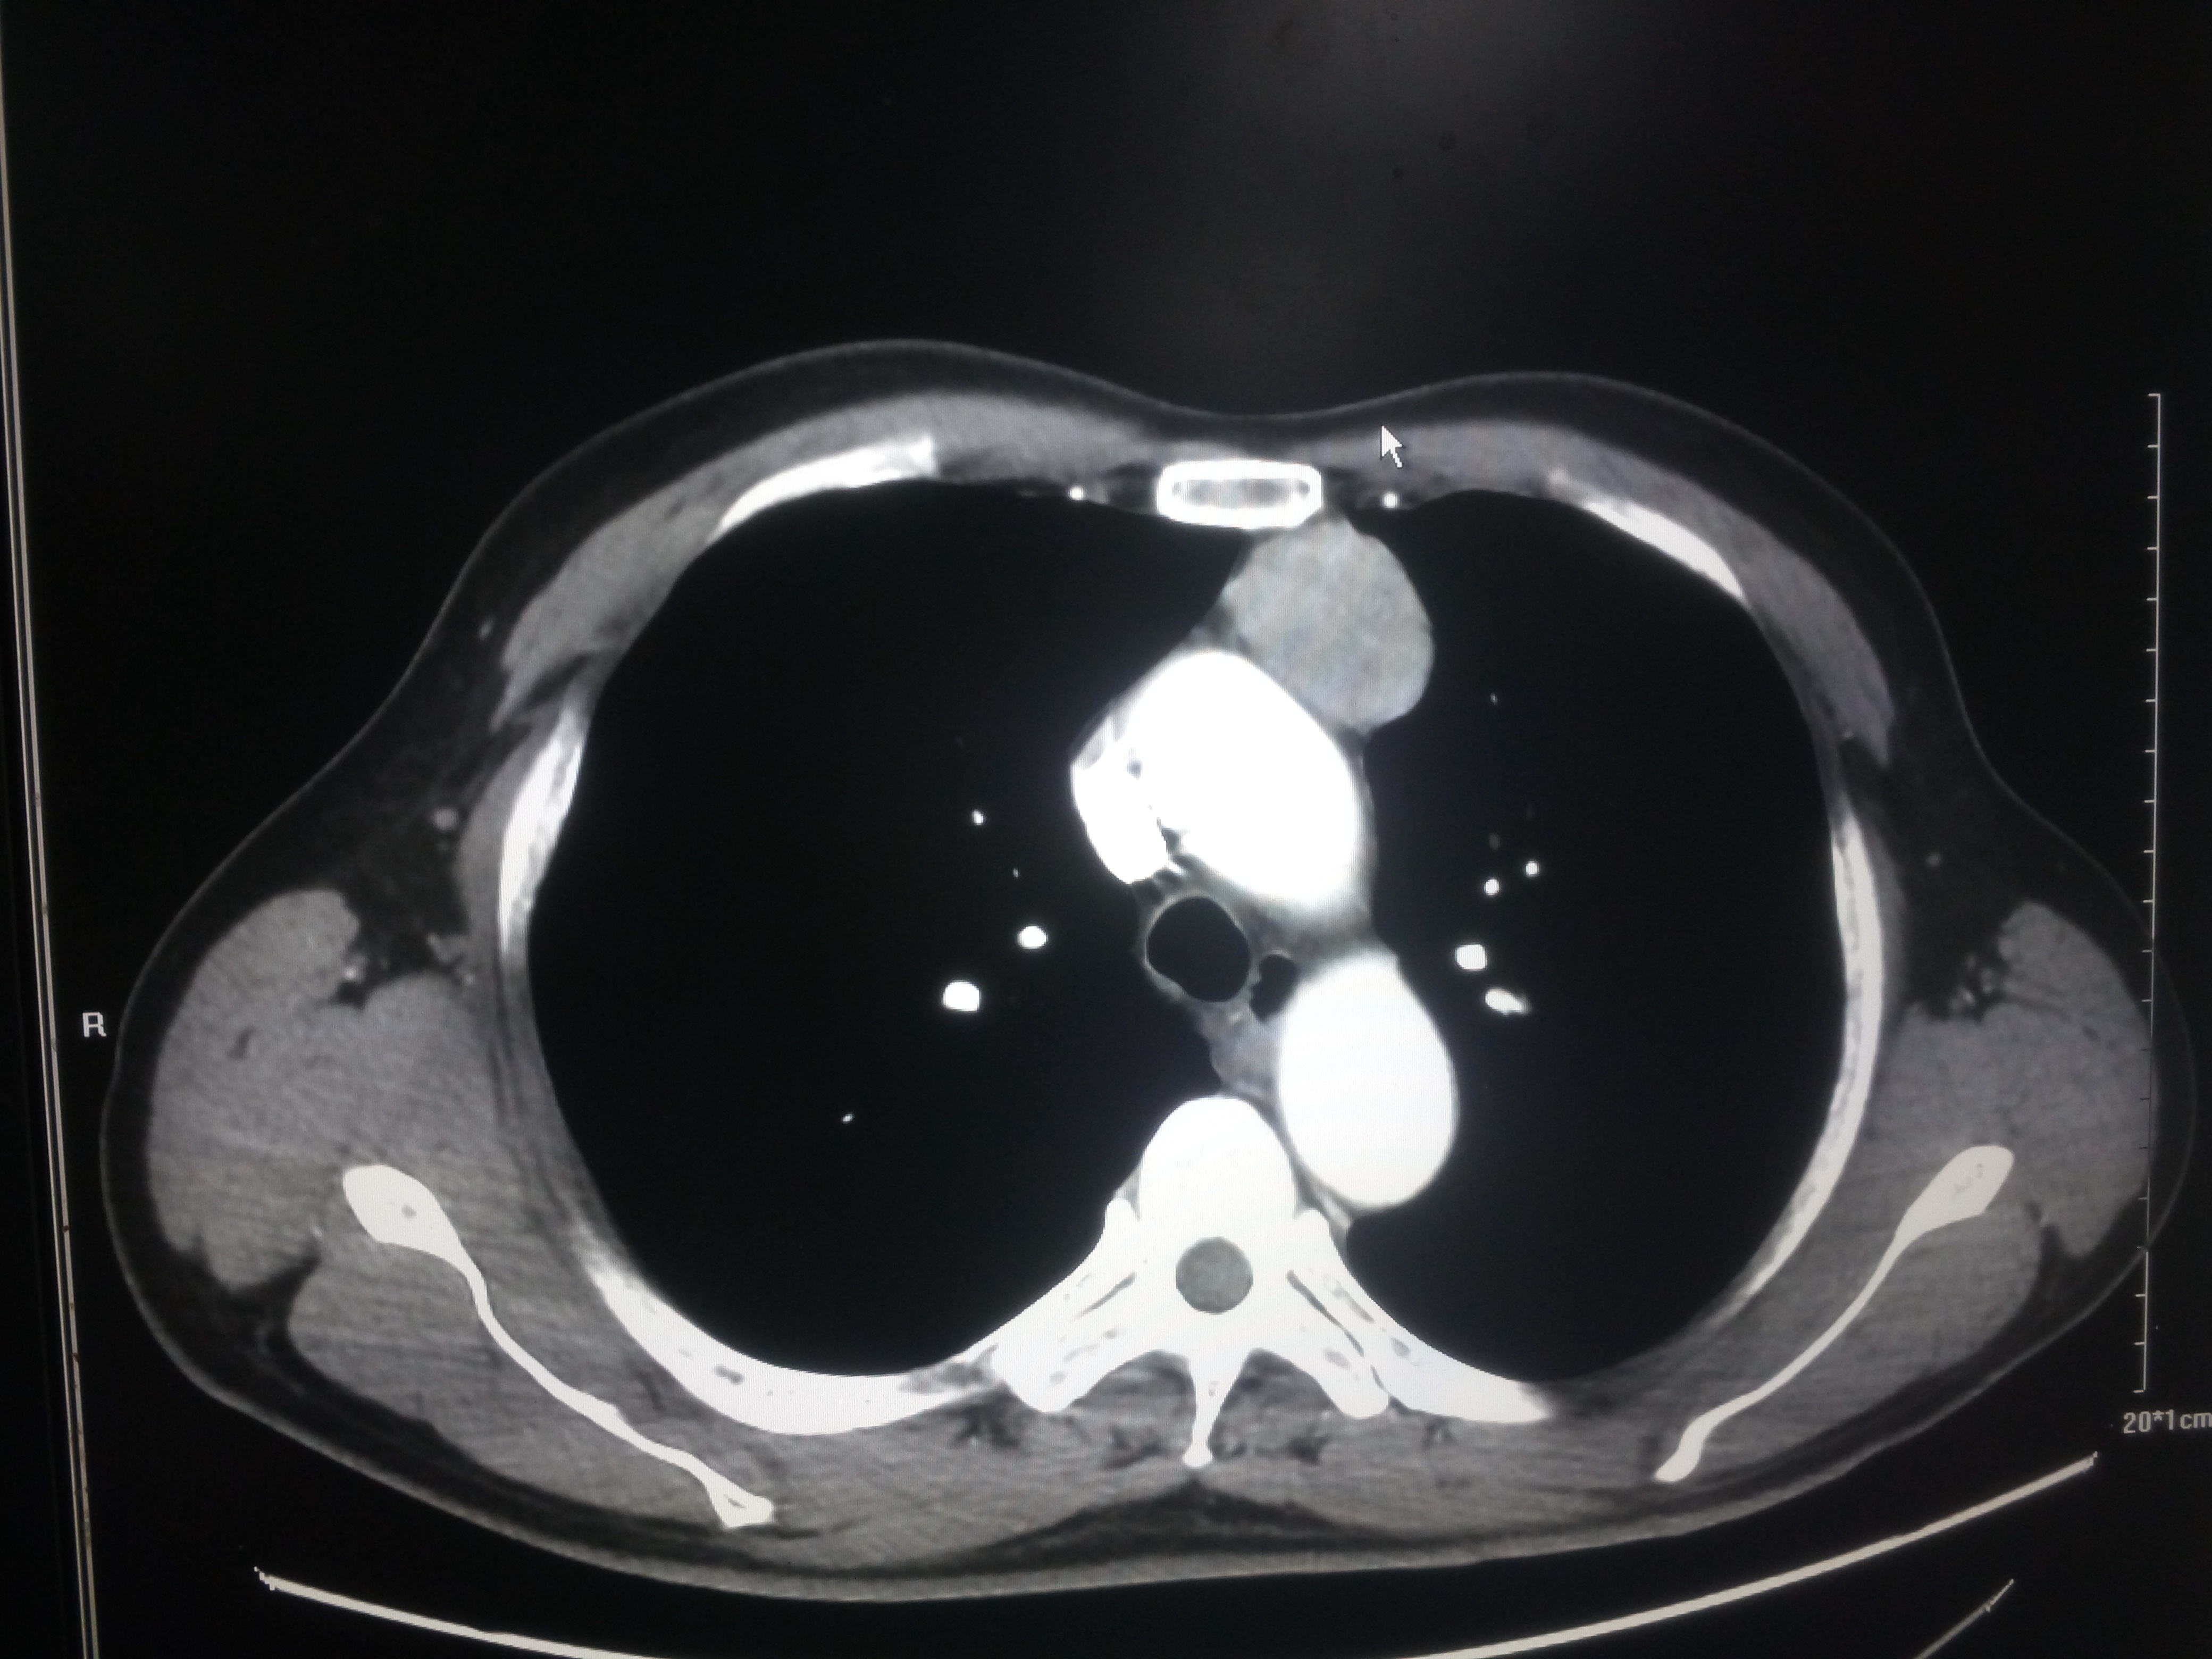

患者“何某某”,男,62岁,因“咳嗽、咳痰6天”于4月2日入住呼吸内科,经进一步检查诊断为“胸腺瘤”,由任军主治医师会诊后转入综合外科治疗。

肿瘤位于上前纵膈向左侧胸腔凸出,大小约4.5X3.5厘米,与升主动脉、心脏、上腔静脉、左侧无名静脉、膈神经毗邻,关系密切,手术难度较大,一旦损伤将会产生严重并发症,甚至危及生命。张元宝主任组织科内讨论并制定了胸腔镜微创手术切除肿瘤的方案,手术由主治医师任军主刀、杨金国配合,术中精细操作,仔细分离,避免损伤,顺利将肿瘤完整切除。